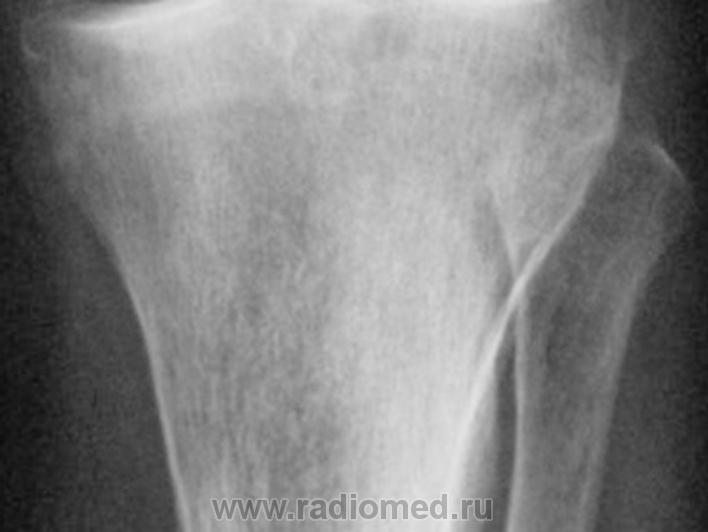

Женщина 75 лет. Жалуется на эпизоды острой боли в передне-внутреннем отделе левого коленного сустава при ходьбе, сопровождающиеся последующими болями в течение 1-3 дней.

И так, что вижу.

1. По всей видимости, необходимо иметь в виду феморо-пателлярный артроз. Конечно, мы не можем оценить ширину суставной щели в феморо-пателлярном суставе, так как боковой снимок сделан не в строгой боковой проекции и суставная щель, как таковая, не дифференцируется. Но можно заподозрить наличие субхондрального склероза - помечен красными стрелками и мелкие субхондральные кистовидные (точечные) просветления - желтые стрелки.

2.Оценивая ширину суставной щели необходимо отметить её неравномерность по ширине - некоторое расширение в латеральных отделах-красные стрелки, по сравнению с медиальными отделами желтые стрелки. Почему расширение латерально, а не сужение медиально? Медиально конгруентность суставных поверхностей сохранена, латерально - конгруентность нарушена - некоторая клиновидность. В области латерального мыщелка б/берцовой кости "намечается" субхондральный склероз - зеленые стрелки.

На фоне суставной щели латерально определяются локальные уплотнения - красные стрелки - локальные обызвествления сумочно-связочных компонентов сустава (по С.А. Рейнбергу), но по всей видимости, это локальные отложения солей Са в "травмированном" мениске, что может свидетельствовать о функцинальной несостоятельности последнего. Точечное уплотнение дифференцируется и медиально - синяя стрелка.

3.Оценивая межмыщелковые возвышения, можно констатировать, что латеральное межмыщелковое возвышение, "кажется несколько больше" (по сравнению с медиальным). Определяется "заострение" и "деформация" вершины латерального межмыщелкового возвышения за счет локального окостенения связки - сиреневая стрелка, что косвенным образом свидетельствует о функциональной несостоятельности этой связки.

4. При анализе проксимального эпи-метафиза б/берцовой кости, локальные участки остеопороза, отмеченные стрелками, связаны, по всей видимости, именно с функциональной недостаточностью мениска и связки, а также с наличием феморо-пателлярного артроза, что функционально выразилось в "недогрузе" латеральных отделов коленного сустава, (возможно даже из-за болевого синдрома, не исключается "подсознательная разгрузка"), и переносе "нагрузки на медиальные отделы.

Уважаемый Валентин Львович всё отлично отметил, я бы хотел добавить, что контуры субхондральной пластинки медиального отдела больше берцовой кости не чёткие, несколько даже волнистые, скорее всего значительные изменения мениска, как следствие болевые ощущения. Ждём МРТ

С точки зрения рентгенолога традиционной ориентации, на рентгенограммах коленного сустава из существенных изменений стоит отметить частичное обызвествление обоих менисков (больше латерального) и субхондрально расположенный линзообразной формы участок то ли остеопороза, то ли остеолиза (лучше виден в задней проекции). Артроза у старушки конечно нет!